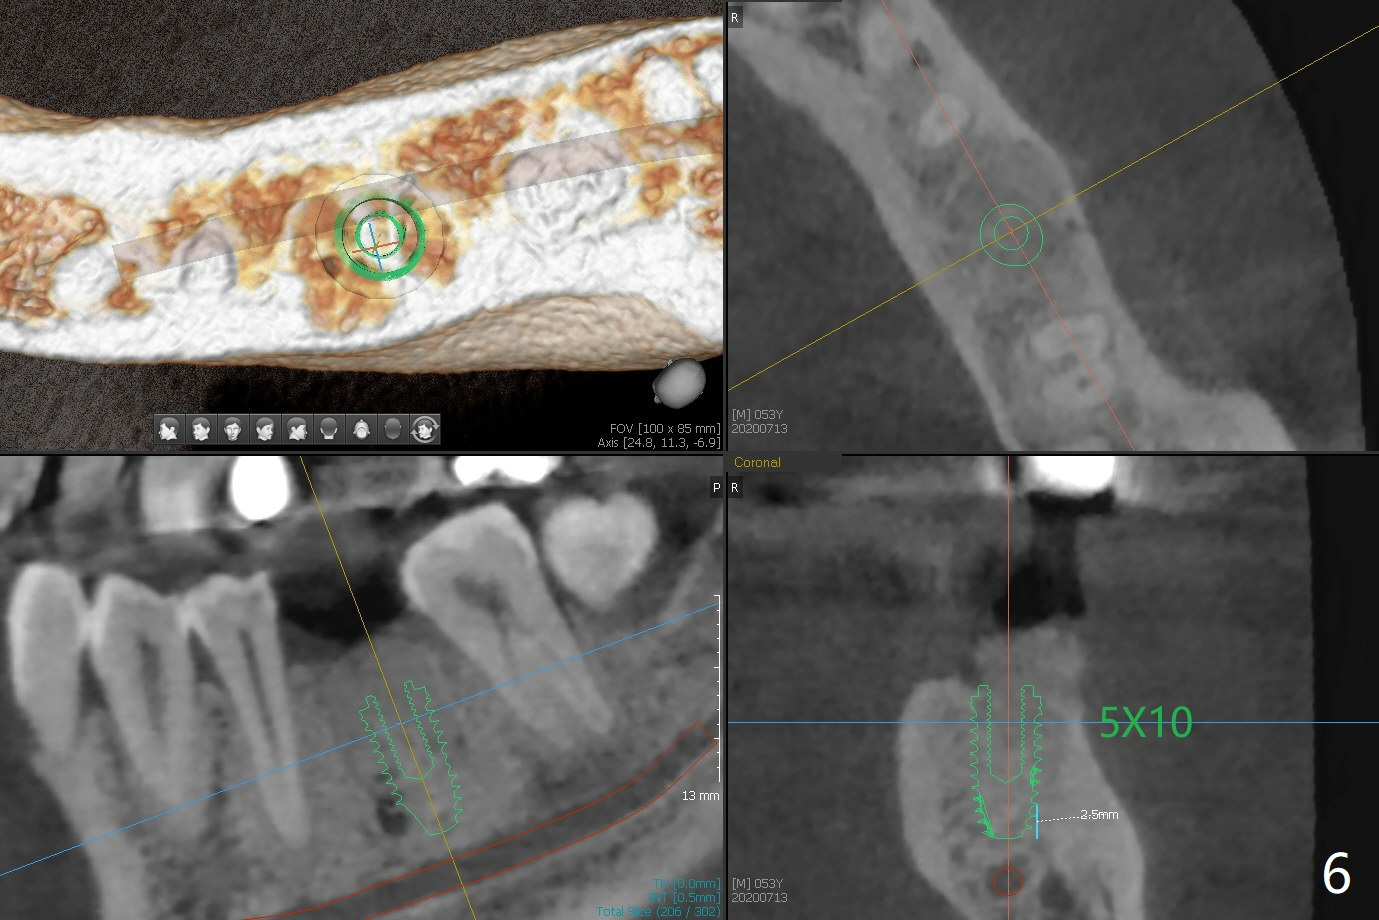

When the patient returns for #15 comp, the bone resorption and swelling at #19 are worse than those 3 years ago (Fig.1,2). After debridement, the mesial socket is large, while the septum is thin, irregular and with undercut (Fig.3). It seems difficult to obtain primary stability for an immediate implant. Vanilla bone and cortical bone hydrated with GEM21 S are placed for socket preservation (Fig.4,5), followed by 12x12 mm BioXclude and 4/0 PGA. In fact the bone height is limited for an immediate implant (Fig.6 (5x10 mm)). There is not enough bone in the septum for primary stability (Fig.7 (cross section of 3D image; L: lingual)). The socket heals 16 days postop (Fig.8). It appears that the granulation tissue is covered by a thin layer of granulation tissue (Fig.9 *), while the membrane remains in place (M). In fact the bone graft remains in the soft tissue zone as well as the hard tissue one (Fig.10). In spite of no apparent loss of bone graft (Fig.4,10), the graft seems to shrink in height 3.5 months postop (Fig.11), while the crest decreases (compare Fig.1 and 11). The keratinized gingiva is wide, but the alveolus reduces in width (Fig.12). The buccal crestal bone is lost 3.5 months postop (Fig.13).